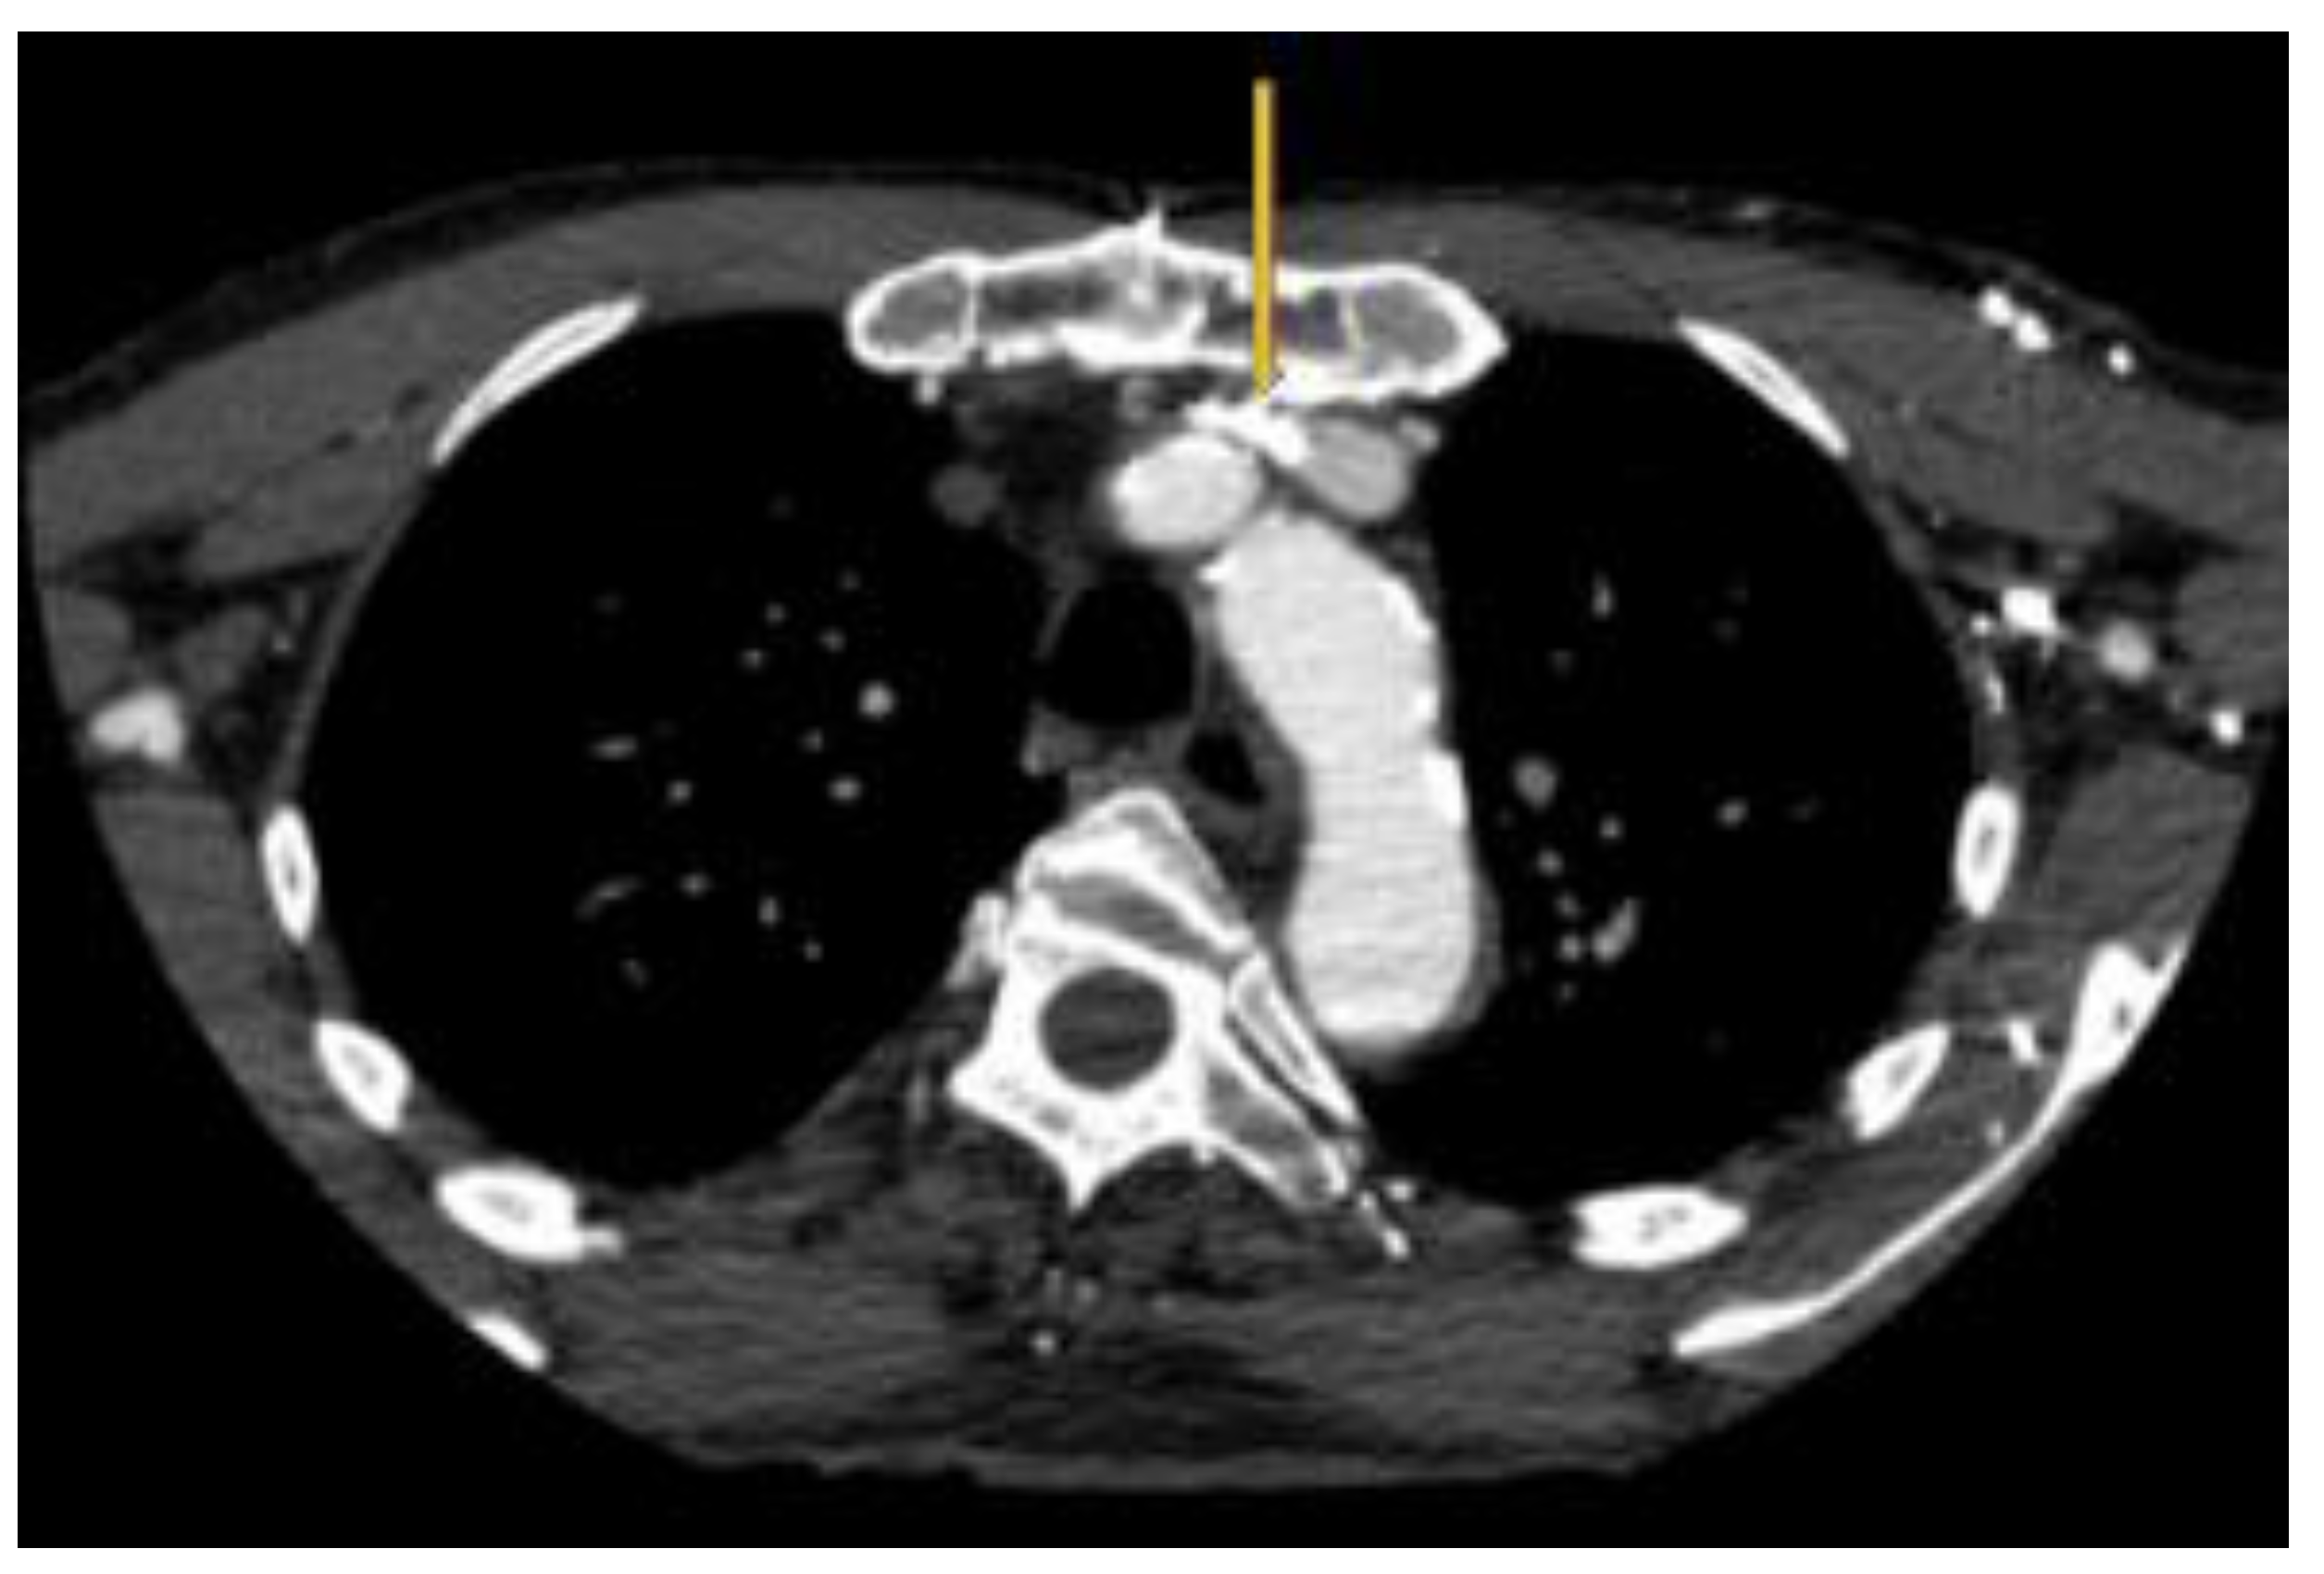

The radiological findings are often obvious but the apparent lack of clinical relevance lends to underreporting. As an example, osteoporotic vertebral fractures suffer a similar fate [8]. There are excellent examples of LBV compression with resultant venous reflux on CT angiography [9,10]. Similar findings are noted on MR Venography [11]. However, this condition will continue to elude detection by CT angiography, if right sided injections are performed [10] and MR venography of the neck if coverage does not extend down to the level of the LBV. Intravascular ultrasound (IVUS) should be the new "gold standard" for diagnosis as it clearly identifies and demonstrates the dramatic decrease in luminal area while providing accurate vessel measurements that are necessary for treatment.

Figure 1. A. Appearance of LBV on intravascular ultrasound with manual demarcation of approximate border with dashed yellow lines B. Severe slit like compression of LBV.